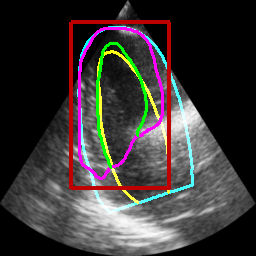

Table II displays the segmentation accuracy computed on the full dataset from patients having good and medium image quality ( patients) for the 4 algorithms described in section Sec. IV-D. Mean and standard deviation values for each metric were obtained from cross-validation on the 10 folds of the dataset. The values in bold correspond to the best scores for each metric. From these results, one can see that all the attention-based networks produced either the same, or better results than the baseline U-Net1, with AG-U-Net and LU-Net being the best performing models. Indeed, AG-U-Net obtained the overall best results for the segmentation of the LVEndo border ( value of mm and value of mm), leading to segmentation scores close but still higher than the intra-observer variability for this structure. The LU-Net-m5 approach obtained the best results for the segmentation of the LVEpi border ( value of mm and value of mm) and the lowest number of geometric outliers (%). Interestingly, these scores are either equivalent or lower than the intra-observer variability for this structure. It is also worth noting the robustness of the LU-Net model with respect to the choice of margin parameter, as margins of % and produce almost the same segmentation scores for all metrics. An illustration of the segmentation performance of the LU-Net-m5 network compared to the baseline U-Net1 model on three different cases is provided in Fig. 2.